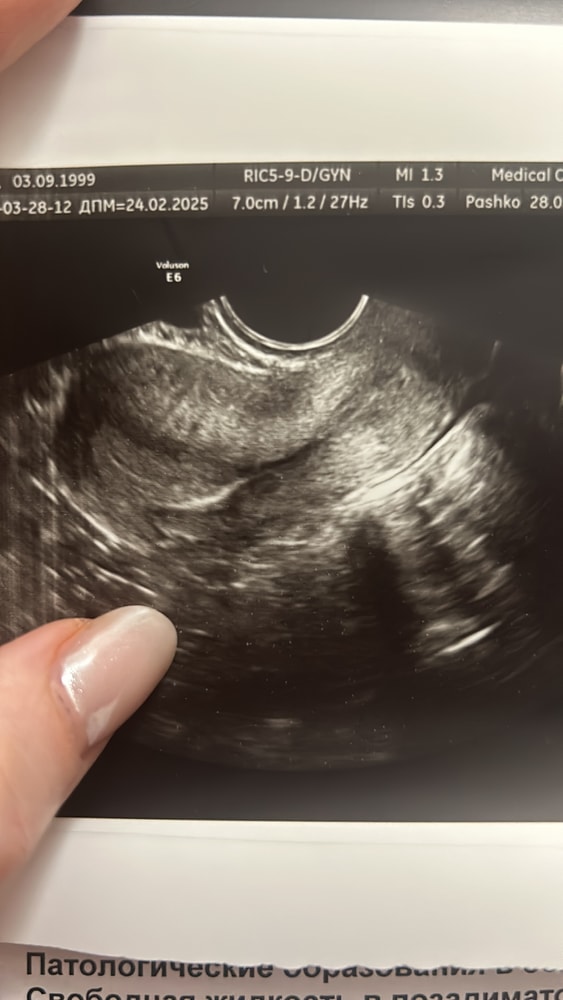

на 2й день задержки месячных хгч был 373 утром, пошла вечером на узи экстренно, так как вышел из меня какой-то кровяной сгусток. Динамику мониторила было:

врач беременность не увидел, эндометрий 9 мм, в яичнике ЖТ которое закровило, отсюда и кровь. Беременности сказали не ждать, что киста выделила хгч. Но я не верю, может срок мал?

Юлия, он не смотрел, только узи, а понял он это только якобы по эндометрию, хотя я незадолго до Б ходила на осмотр матка была обьемом 26,7, сейчас 30,4 - увеличилась